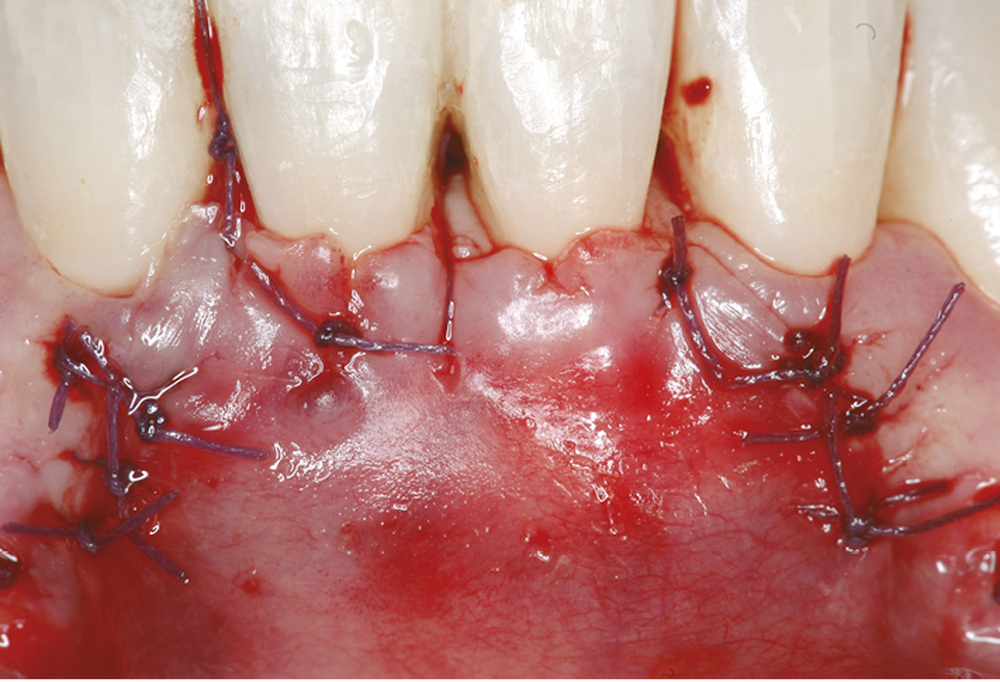

En plus du contexte parodontal, le type de mouvements orthodontiques envisagés est à considérer. Dans le secteur incisivo-canin mandibulaire, un des objectifs classiques du traitement orthodontique est le repositionnement de l’incisive dans un axe compatible avec des relations inter-arcades harmonieuses (≤ 95°). Dans certains cas, l’objectif à atteindre peut se traduire par un mouvement de la racine vers le vestibule. Ce mouvement est considéré comme à risque et peut aggraver une situation parodontale initiale non favorable. Face à une situation clinique complexe, il est possible de synthétiser les facteurs positifs et négatifs et considérer que l’accumulation de deux facteurs négatifs conduit à la recommandation d’adresser le patient chez un parodontiste (tableau 1).